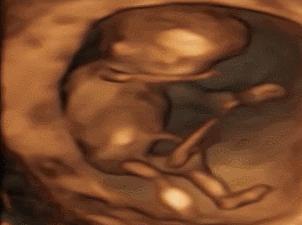

菌菌告诉你,小家伙不仅会做各种动作,表情更是丰富的不得了。

小脑袋一晃一晃的,我不答应,我不高兴,我要吃肉肉……

咦,妈妈在外面跟我说话,嘟嘴卖个萌先。

哈哈,妈妈肯定是被我萌到了,我都听到她的笑声了。

我还会吐舌头、扮鬼脸!